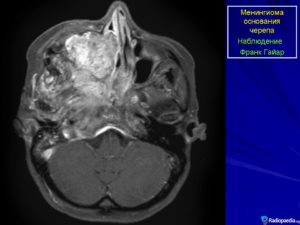

Менингиома располагается вдоль основания черепа и оболочки венозных синусов. Очень часто она встречается в парасагиттальном синусе, затылочном отверстии, в области больших полушарий мозга и мостомозжечковом углу.

Наиболее часто внутричерепные менингиомы располагаются парасагиттально и на фальксе (25%). Конвекситально в 19% случаев. На крыльях основной кости — 17%. Супраселлярно — 9%. Задняя черепная ямка — 8%. Ольфакторная ямка — 8%. Средняя черепная ямка — 4%. Намет мозжечка — 3%. В боковых желудочках, большом затылочном отверстии и зрительном нерве по 2%.

По локализации менингиомы:

- конвекситальная;

- парасагиттальная;

- серповидного отростка;

- тенториальная;

- менингиома фалькса;

- кавернозного синуса;

- теменной области;

- опухоль зчя – с поражением основания черепа;

- передней черепной ямки;